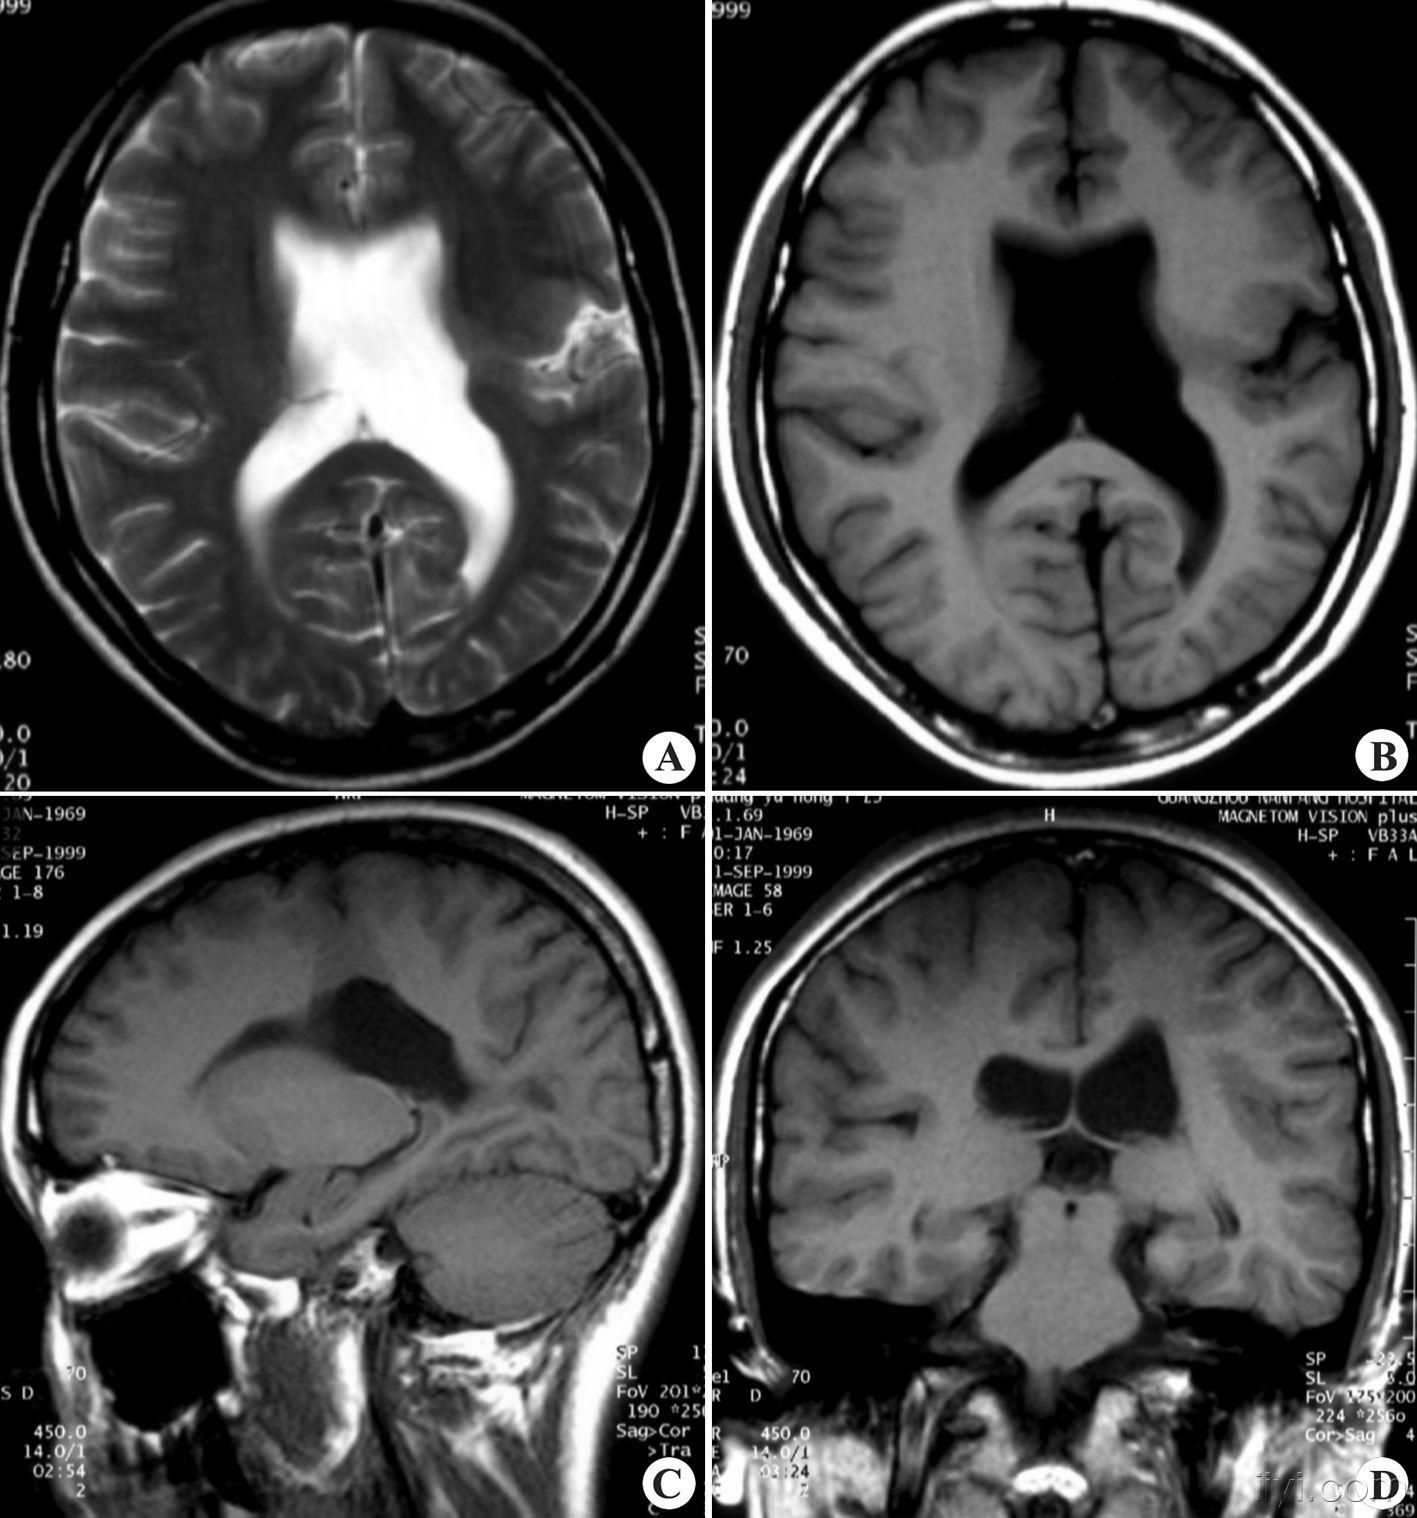

看图说话1脑灰质异位脑裂畸形

图片尺寸1417x1518

先天性脑裂畸形

图片尺寸600x600

原创共享典型小儿颅脑先天畸形脑裂畸形

图片尺寸864x864